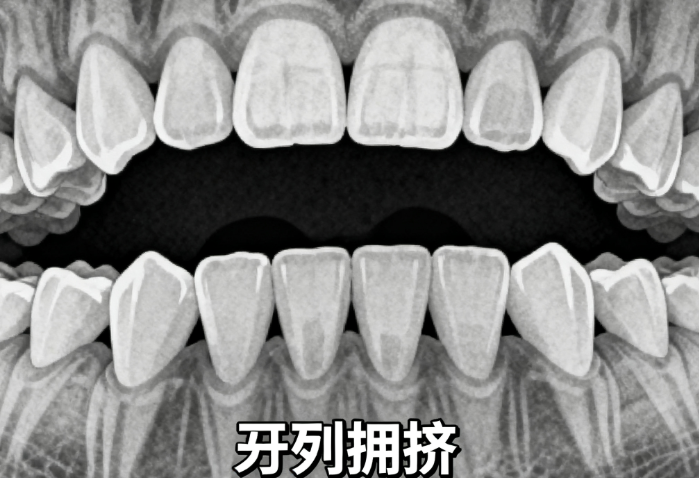

2. 从业经验:从医以来累计完成2000+正畸实例,覆盖青少年早期矫治、成人牙列拥挤、地包天等多种类型,其中不拔牙矫正实例占比超60%,擅长通过稳准评估骨量与牙弓潜力,避免拔牙对牙齿及牙周的损伤。

3. 实例验证:2000+实例中,不少患者是“牙列拥挤但骨量足够”的情况——比如一位18岁患者,中度拥挤,张医生通过扩展上牙弓3mm、调整下牙轴向,18个月后排齐牙齿,无需拔牙,疗效稳定。